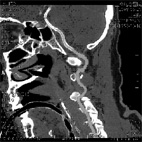

在所有此類病患中,基底動脈腦梗塞,不僅死亡率高達在第十八時以上,同時倖存的病患呈現重度昏迷狀態,且以往的治療方式有其侷限。本院在去年六月,成功的治療一位五十二歲正值黃金時節的壯年男性,將其完全阻塞的基底動脈,如下圖一及圖五。不僅有效的打通阻塞血管(國內外的文獻上尚無支架置放如此長度的報告),而且病患三個月後迅速恢復生活自理和相當程度的工作能力,使得團隊在腦中風全方位治療上,邁向新的里程碑。

圖五電腦斷層顯示支架置放長達十公分